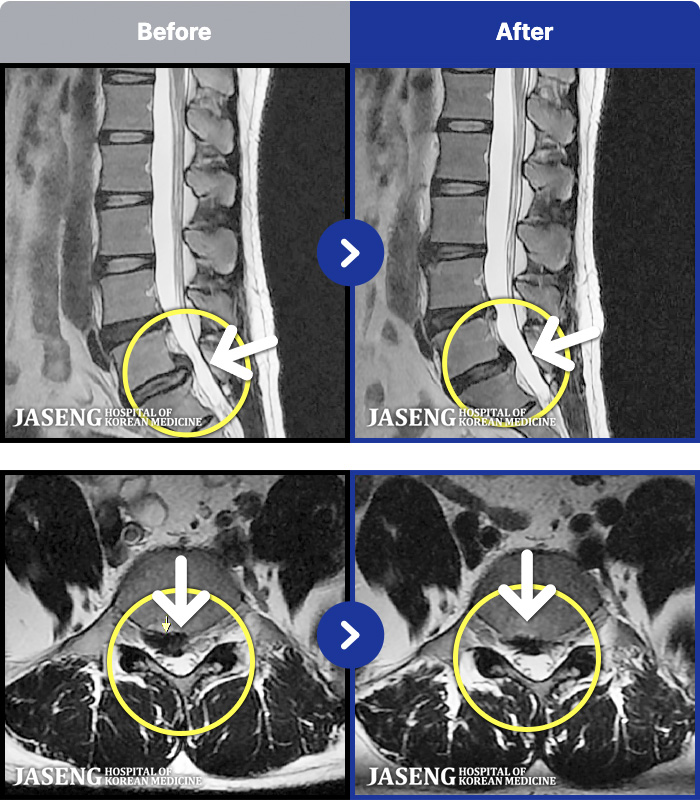

MRI ġ

MRI ũ ʸ Ȯϼ.